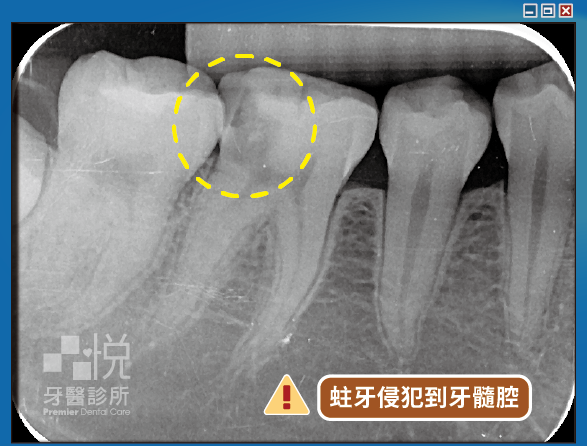

當蛀牙細菌感染神經腔與神經管後,一開始會因為牙髓炎而感到劇痛,但隨著神經壞死就不痛了。細菌會持續滋生擴散至牙根尖造成牙根尖感染,就會在根尖牙齦反覆產生膿包。